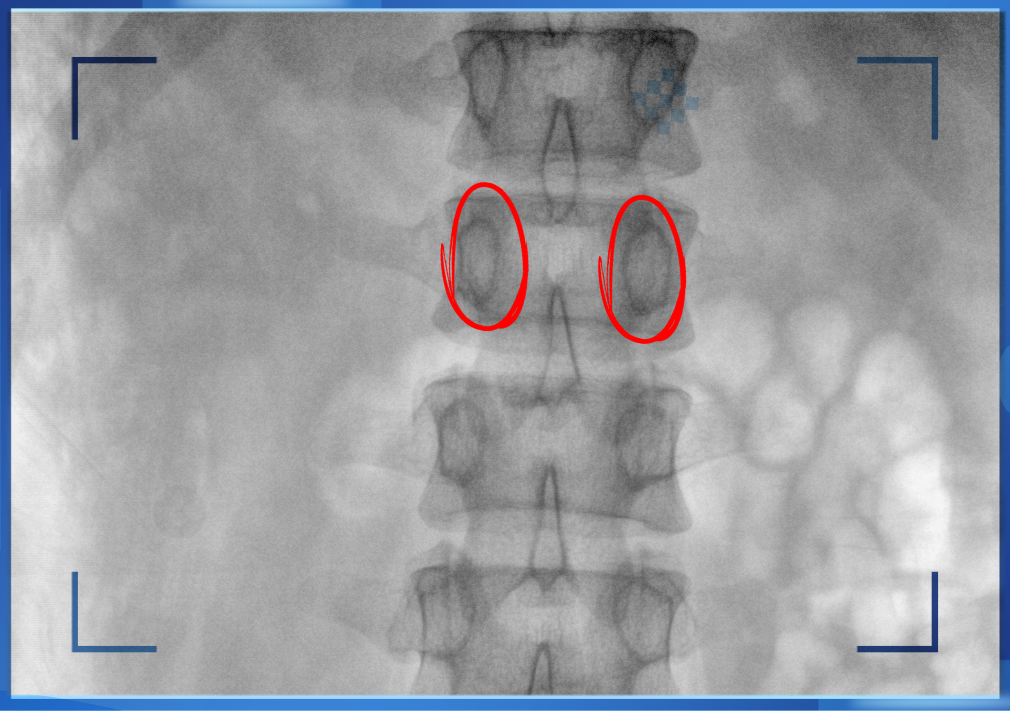

醫(yī)生通常會(huì)在“貓眼”里尋找進(jìn)針點(diǎn)和出針點(diǎn),憑醫(yī)生的經(jīng)驗(yàn)把釘子打在椎弓根里。手術(shù)比較依賴醫(yī)生的經(jīng)驗(yàn),萬(wàn)一出現(xiàn)偏差對(duì)病人來(lái)講就是毀滅性的打擊。如果在復(fù)雜的手術(shù)中有三維影像的支持,確保釘子精準(zhǔn)的打在椎弓根里,可大大的提高手術(shù)操作的精度。

“貓眼”指的是椎弓根在正位的投影。